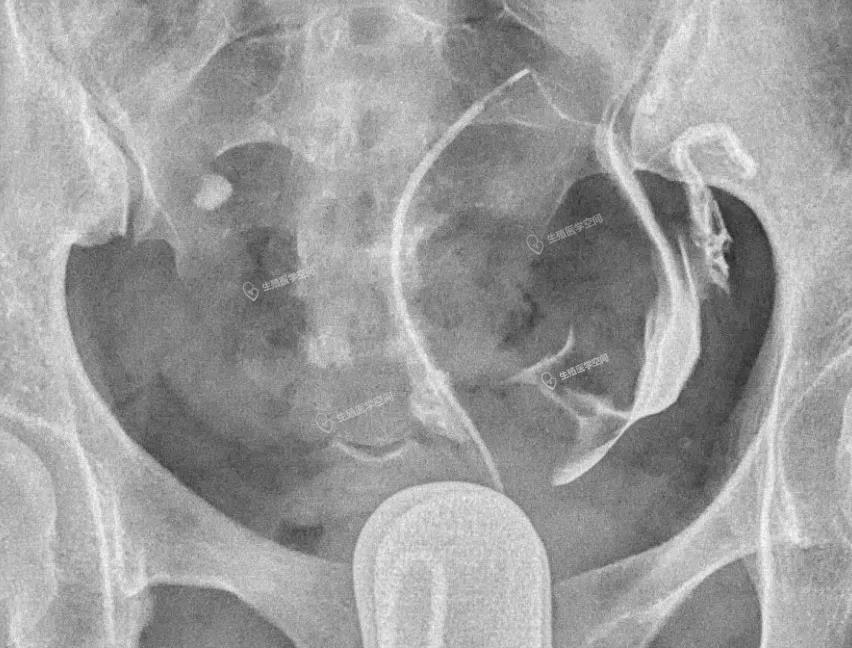

病例3 女 22岁 继发不孕,子宫输卵管造影发现双侧输卵管伞部阻塞。男方检查均正常。通过造影片初步评估输卵管粘膜功能好,于是做腹腔镜手术。术后第5个月怀孕,后来足月妊娠,自然分娩一健康婴儿。